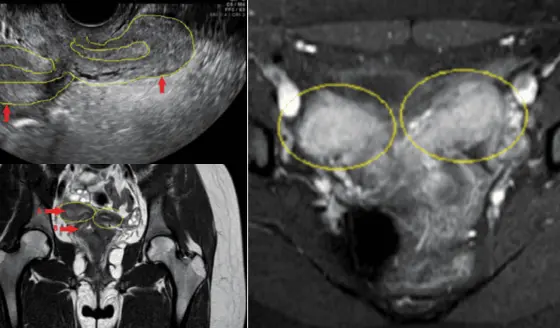

Dolor pélvico agudo y sangrado en adolescente: Resonancia revela útero doble y agenesia renal ipsilateral